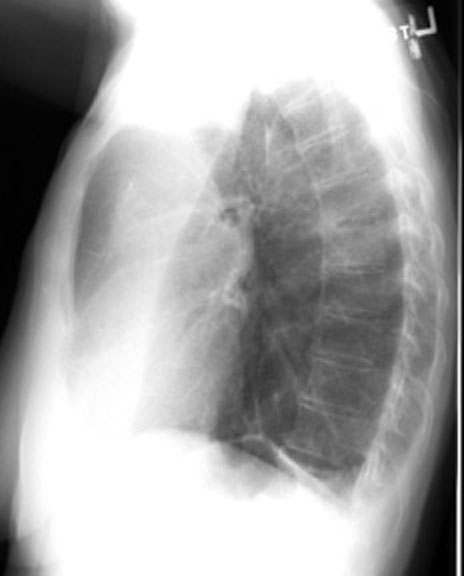

• You need a lateral view to appreciate the movement of oblique fissures. Forward movement of oblique fissure in LUL atelectasis.

LUL Atelectasis

Bronchogenic carcinoma